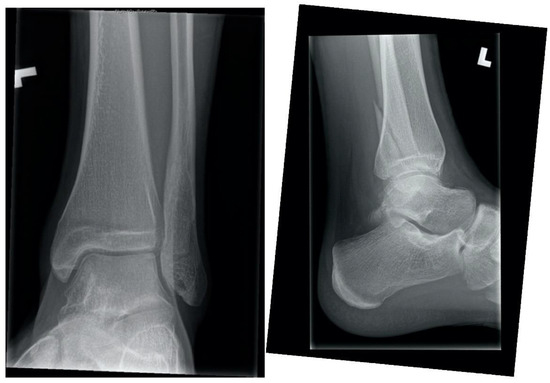

Initial treatment was circumferential casting and non-weight bearing. At one-week post-injury X-rays confirmed near-anatomic alignment. At four weeks post-injury radiographs were equivocal for callus, the patient’s exam was reassuring, and a removable cast-boot was placed with progressive weight bearing. At eight weeks post-injury, there was pain at the fracture site and inability to bear full weight. The patient was counselled to discontinue EC use. Cast-boot immobilization with weight bearing as tolerated was continued. There was no clinical or radiographic change at twelve weeks post-injury (Figure 1). Delayed union was diagnosed in the absence of healing beyond the expected four to six weeks required to heal this injury [1]. At eighteen weeks post-injury the fracture was no longer symptomatic, and radiographs confirmed bony union.

Figure 1.

Twelve-week ankle radiographs demonstrating no radiographic union after fibula fracture in a pediatric electronic cigarette user.